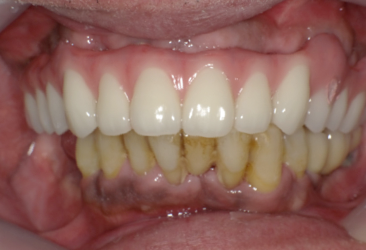

術後の写真です。フレアーアウトした分、歯を引っ込めてかみ合わせも若干高くしています。

術前の口元と別人になっているのが分かると思います。

オールオンフォーの良いところはこのように好きなように歯を並べることができることです。